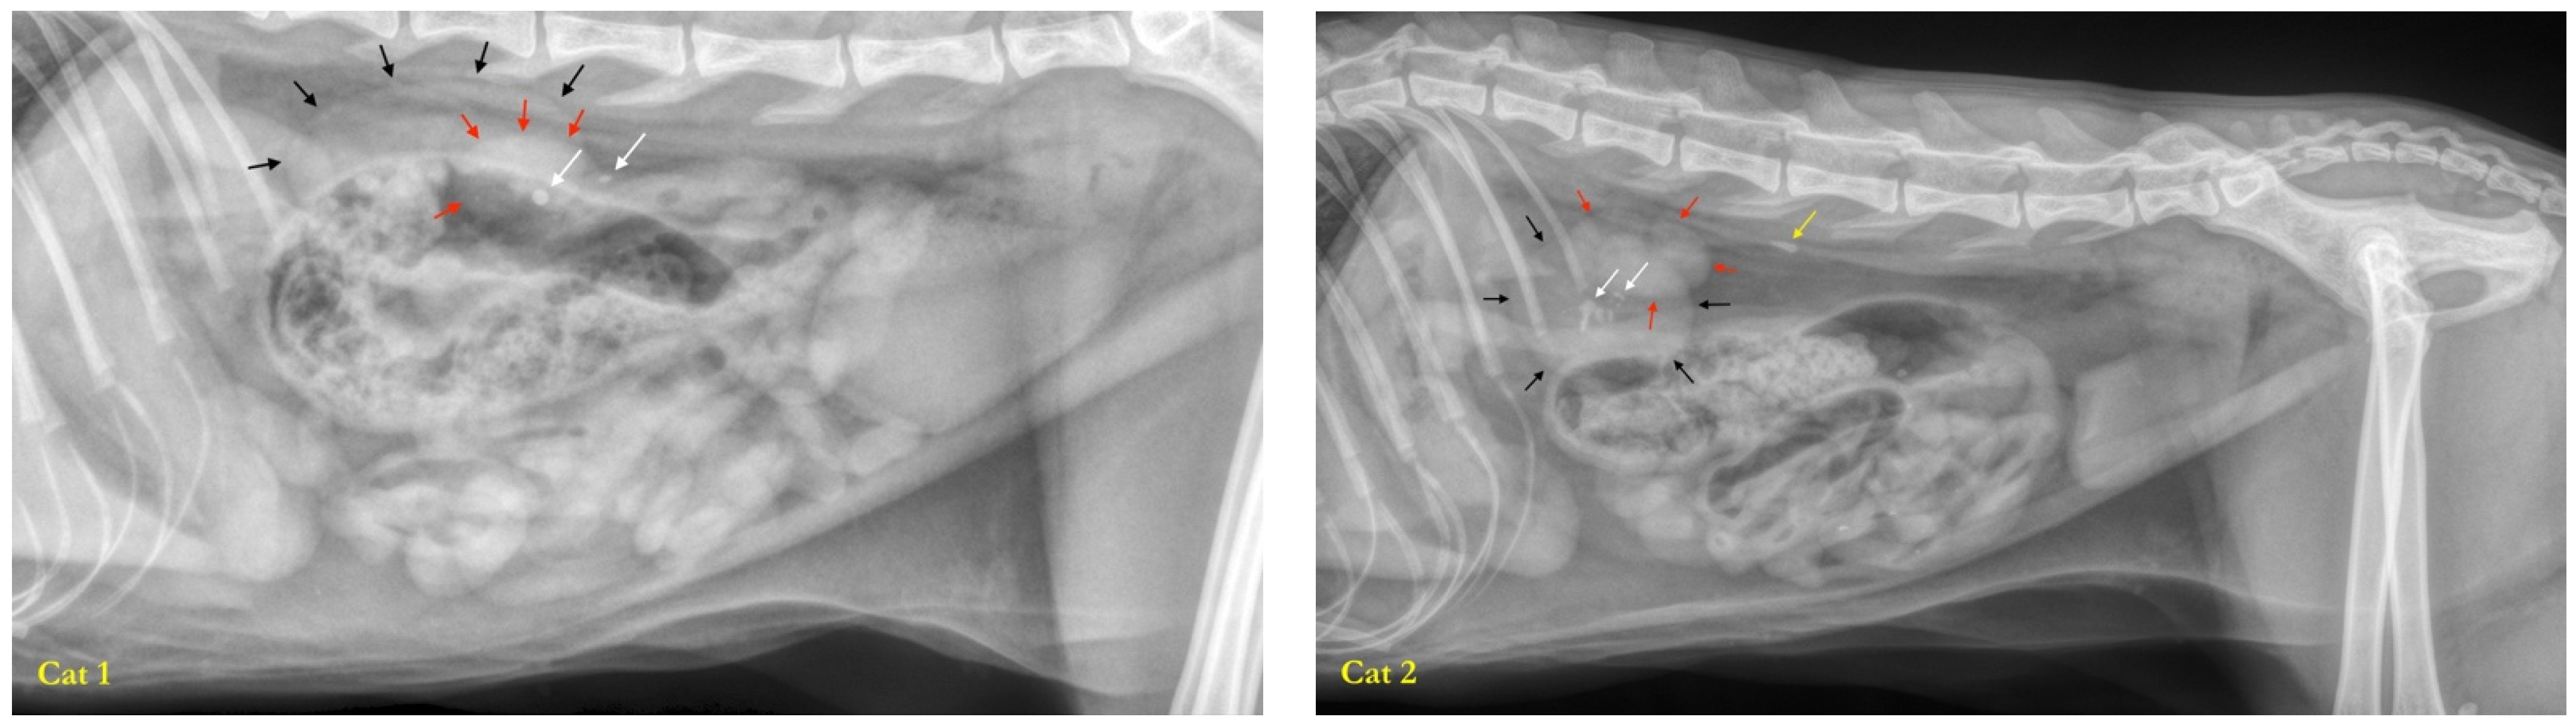

3.1. Studied Population

3.2. Characterization of the Fecal Microbiota